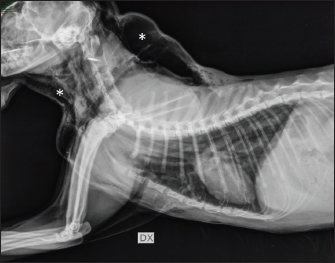

On arrival, venous blood gas analysis revealed mild respiratory acidosis and mild hyperlactatemia (Table 1). The complete blood count revealed moderate thrombocytopenia and neutrophilic leukocytosis (Table 2). Biochemical analysis showed elevated liver and muscular enzyme levels and increased serum amyloid A levels (Table 2). Hypofibrinogenemia (1.36 g/l) with unremarkable coagulation time was evident. All abnormalities were consistent with the traumatic event suspected. Thoracic radiographs confirmed the presence of severe subcutaneous emphysema, associated with moderate pneumomediastinum and mild pneumothorax (Fig. 1). Computed tomography (CT) was scheduled for the following day due to the high suspicion of tracheal injury associated with cervical compressive myelopathy. The cat was hospitalized at the intensive care unit under strict monitoring, minimizing manipulation as much as possible. Fluid therapy was set at 2 ml/kg/h IV of lactated Ringer’s solution, together with analgesic therapy with methadone at 0.1 mg/kg IV every 4 hours, and antibiotic therapy with ampicillin-sulbactam 20 mg/kg IV every 8 hours. The cat was mildly symptomatic for the pneumothorax and was therefore managed conservatively. The following day, the clinical parameters were stable, and a progressive reduction of the subcutaneous emphysema and pneumothorax was noted; therefore, the patient was sedated with 0.2 mg/kg of methadone intravenously (IV) and 2 µg/kg of dexmedetomidine IV, and then placed in a VetMouseTrapTM to avoid intubation and general anesthesia. CT scans confirmed the moderate to severe subcutaneous emphysema, pneumomediastinum, and mild pneumothorax (Fig. 2). A dorsal parietal deformation of the cervical trachea of approximately 1 cm in length was observed, causing a mild reduction in the dorsoventral tracheal diameter. There were no other airway injuries. An incomplete fracture line of the caudal margin of the C4 vertebral arch was observed. The fracture line appeared slightly left-lateralized, with a caudal bone fragment approximately 2 mm long and 5 mm wide. This fragment was dislocated into the vertebral canal, narrowing the dorsoventral diameter, with subsequent compression of the spinal cord (Fig. 3). The CT scan confirmed the suspicion of C4 vertebral fracture and tracheal rupture. Endoscopic evaluation of the upper airways and surgical treatment with a dorsal approach for spinal decompression were scheduled for the following day.

Fig. 3. Longitudinal (A, C) and transverse (B) CT images acquired with the cat placed in the VetMouse TrapTM. Incomplete fracture line of the caudal margin of the fourth cervical vertebral arch (green arrow). The fragment is dislocated into the vertebral canal, narrowing the dorsoventral diameter with subsequent compression of the spinal cord.